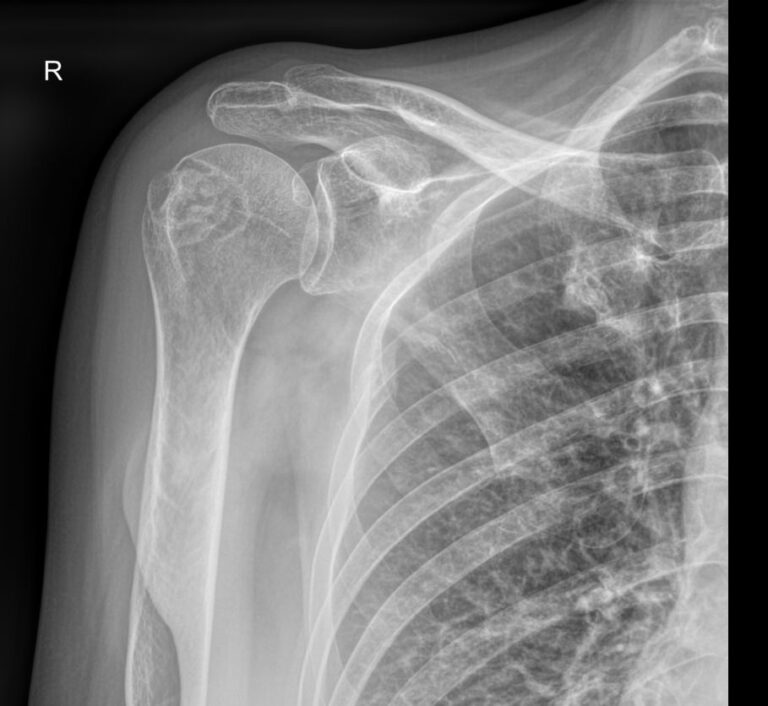

Рентгенография относится к стандартным методам диагностики плечевых суставов. На снимке можно обнаружить все патологические изменения, произошедшие в данной области, а также стадии болезни. Рентген используется также для выбора метода лечения и его контроля. Рентгеновское оборудование последнего поколения позволяет делать серию снимков с минимальной дозой облучения. Это важно, так как дает возможность выполнить необходимое количество снимков в динамике.

Снимки выполняются в разных проекциях, в зависимости от того, какой элемент сустава требуется визуализировать.

• Костно-травматические изменения ― переломы, вывихи, остеофиты;

• Состояние суставных поверхностей ― не нарушено, эрозии;

• Суставные щели ― сужение, обызвествление капсулы, наличие выпота;

• Изменения в костных тканях ― изменений нет или наблюдаются разные патологии;

• Изменения в мягких тканях ― отечность, инородные тела;

• Новообразования любой природы.